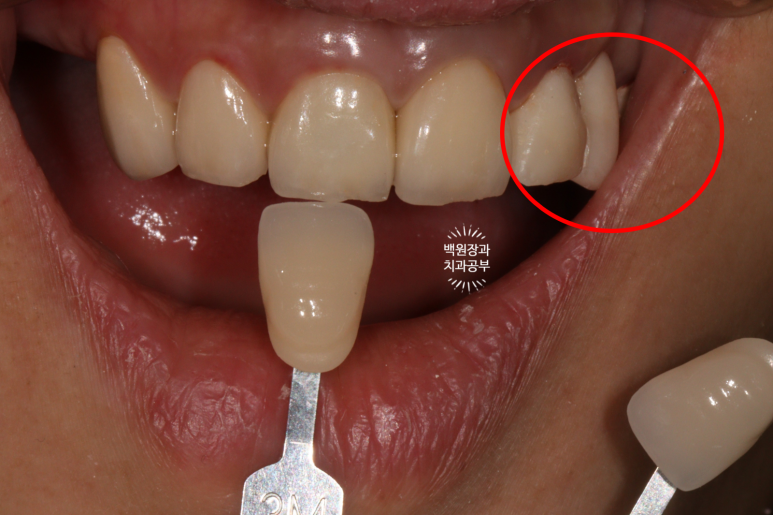

빨간색으로 표시해둔 것이 임시 지르코니아 브릿지입니다.

사실 좀 못생겼지만.. 사회생활 하시는데 지장 없을 정도는 됩니다!

원하시는 치아 색상을 파악하기 위해, VITA shade guide 를 가지고 환자분과 함께 색상을 정해봅니다.

보통 앞니는 조금 더 밝은색을 선호하시는 듯 해요.